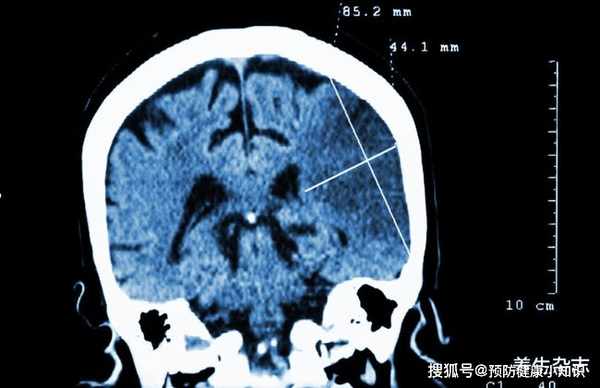

可就在前兩天,陳大爺吃過飯後剛起身,就突然暈倒在地,家人馬上把他送到了醫院做檢查,竟然被查出來換了腦梗。

在檢查時醫生也發現陳大爺的血生化、膽固醇以及低密度脂蛋白均增高,就是我們平時說的血脂高。

再加上陳大爺長時間的大量飲酒,導致出現血管動脈硬化、狹窄及腦栓塞等情况。